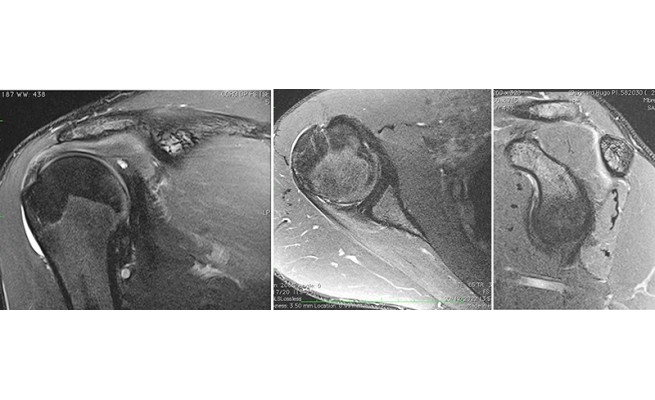

Le syndrome de Parsonage Turner est une mononeuropathie ou une polyneuropathie des nerfs du plexus brachial. Cette neuropathie demeure inexpliquée même si on évoque une origine virale ou auto-immune. Elle touche dans la majorité des cas le nerf supra-scapulaire (supra-épineux et infra-épineux), le nerf axillaire (deltoïde et teres minor) et le nerf subscapulaire inférieur et supérieur.